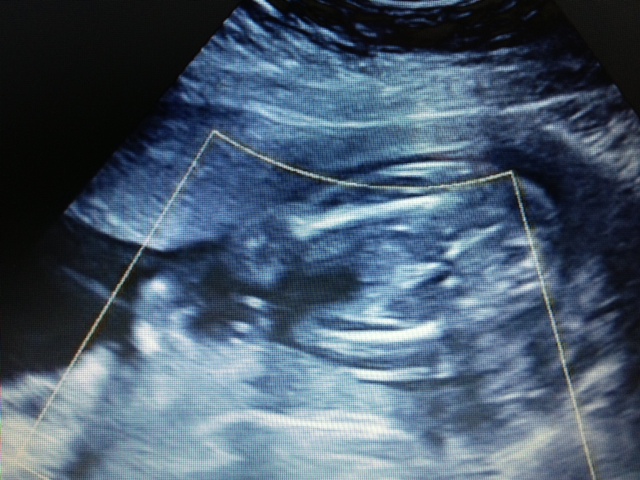

I have just posted a nub picture from my 12 week scan. This is a shot from the 20 week scan. I think its the baby's front but really am not sure - it may be a potty shot!!

This is a shot up through baby's pelvis so no way to determine gender.